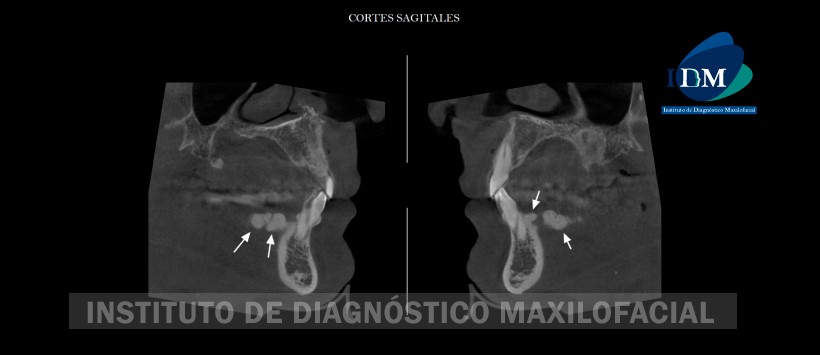

A la evaluación de la tomografía volumétrica (CBCT) en cortes coronales (Figura 2), sagitales (Figura 3), axiales (Figura 4) y transaxiales (Figura 5, 6 y 7) se evidencia presencia de múltiples excrecencias óseas de forma lobulares localizados en reborde alveolar de tabla ósea lingual en zonas de piezas 35, 34, 33, 32, 43, 44 y 45; compuesto por presencia de hueso compacto. Por otro lado, se visualiza una excrecencia ósea de hueso compacto de una amplia base localizada en rafe medio del paladar. Así mismo, se aprecia la presencia de excrecencias en el extranjero al nivel de la tabla ósea vestibular en zonas de piezas 17, 13, 23 y 26.